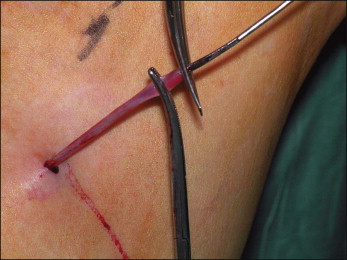

Subarachnoid block (spinal) or general anesthesia is used when classic stripping operations are performed. In the majority of patients, the GSV may be removed using two small incisions. One incision in the groin crease just medial to the femoral pulse usually allows easy exposure of the proximal GSV and saphenofemoral junction ( Fig. 10.9 ). The incision should be large enough to provide adequate exposure to allow a complete and safe procedure, particularly in obese patients, but is usually 3 cm or less in length. The incision should not be made inferior to the groin crease since an inappropriately inferior incision would make control of branches other than the GSV more difficult.